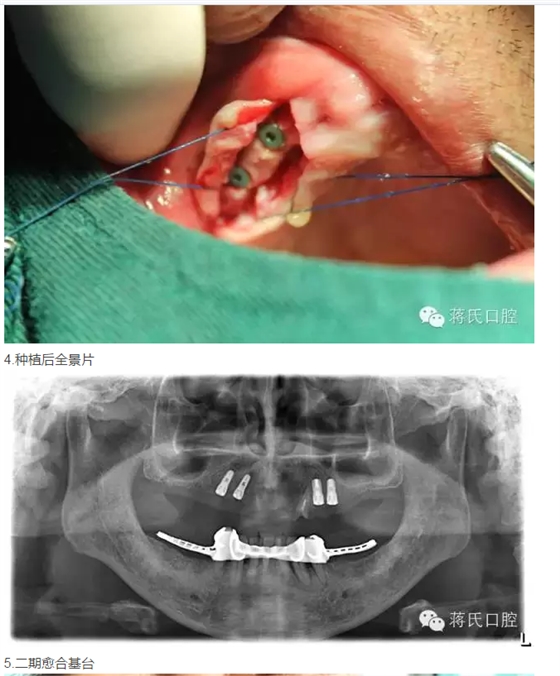

治療過程

修復(fù)前全景片

3兩側(cè)四五區(qū)種植共4顆

4活動(dòng)義齒雙重冠修復(fù)

6時(shí)間 4個(gè)月